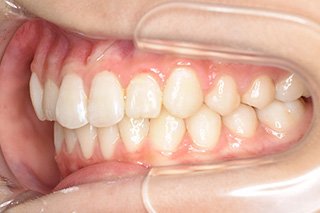

顎顔面矯正症例 11歳女児 Case

| 主訴 | 永久歯が変な所からはえてきている|顔貌 | |

|---|---|---|

| 施術内容 | 矯正1期治療 | |

| 治癒期間 | 1年5ヶ月間 | |

| 費用 | 459,200円(税込) | |

| リスク・ 副作用 | 痛みを伴う | |